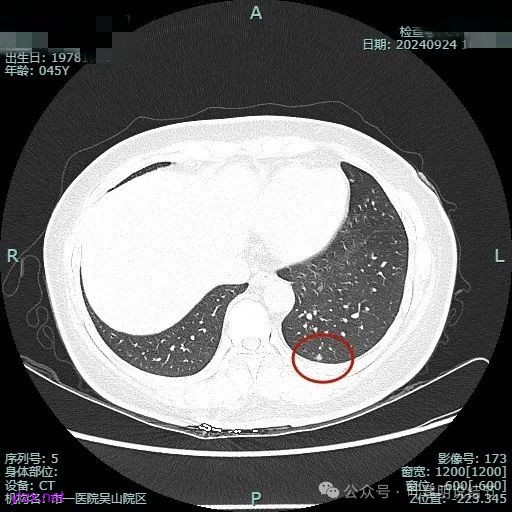

病灶3:

左下叶基底段微小结节,也是混合密度偏实性,瘤肺边界稍不清,与右侧的是类似形态的。

病灶混合密度,但瘤肺边界不够清楚,灶内也不太致密。

整个显得有点模糊,虽有血管进入,但血管说不上显著异常增粗,病灶边缘有细毛刺,贴胸膜近,但缺乏明显收缩力。

病灶显糊,轮廓较清但瘤肺边界欠清晰。

有血管进入,但病灶的感觉总好像缺乏收缩力,也聚拢性不太够。